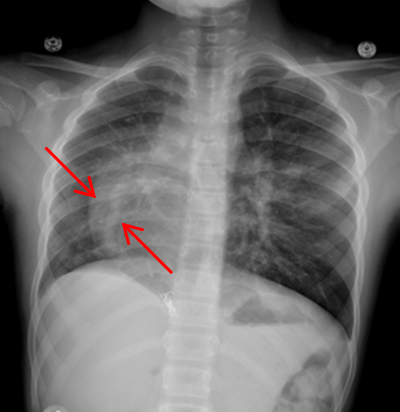

Routine laboratory analysis, including a complete blood count and metabolic panel, is normal. A postero-anterior chest roentgenogram is shown in Figure 1. Chest computed tomography (CT) without IV contrast (Figure 2), and gadolinium enhanced magnetic resonance angiogram (Figures 3 and 4) are also obtained. A decision is made to perform a cardiac catheterization (Figures 5 and 6) for further evaluation.

Figure 1

Scimitar syndrome or congenital venolobar syndrome is a rare congenital heart disease characterized by drainage of partial anomalous pulmonary veins of the right lung (often middle and lower lobes) into the inferior vena cava (IVC). This makes a crescent-shaped shadow parallel to the right heart border, likened to the scimitar sword, on chest roentgenography (Figure 7). Patients with scimitar syndrome also have some hypoplasia of the right lung with associated dextro-position of the heart. Aortopulmonary collateral vessels and atrial septal defects are also commonly seen in patients with Scimitar syndrome in addition to extracardiac anomalies.1,2,3

The red arrow (Figures 7, 8, 9, and 11) shows a large scimitar vein. Chest CT (Figure 8) shows partial anomalous pulmonary venous return from the right lower pulmonary vein into the inferior vena cava (IVC) and right-sided pulmonary hypoplasia with consequent dextro-position of the heart into the right hemithorax. The gadolinium-enhanced angiography cardiac magnetic resonance imaging (MRI) (Figure 9) with three-dimensional reconstruction (Figure 10, Video 1) confirms the diagnosis, which shows aortopulmonary collaterals from the descending abdominal aorta to the right lower lung lobe (one dot), large anomalous pulmonary vein, the scimitar vein (two dots), draining the right lower lung to the IVC (three dots). The right heart is within normal limits for size.